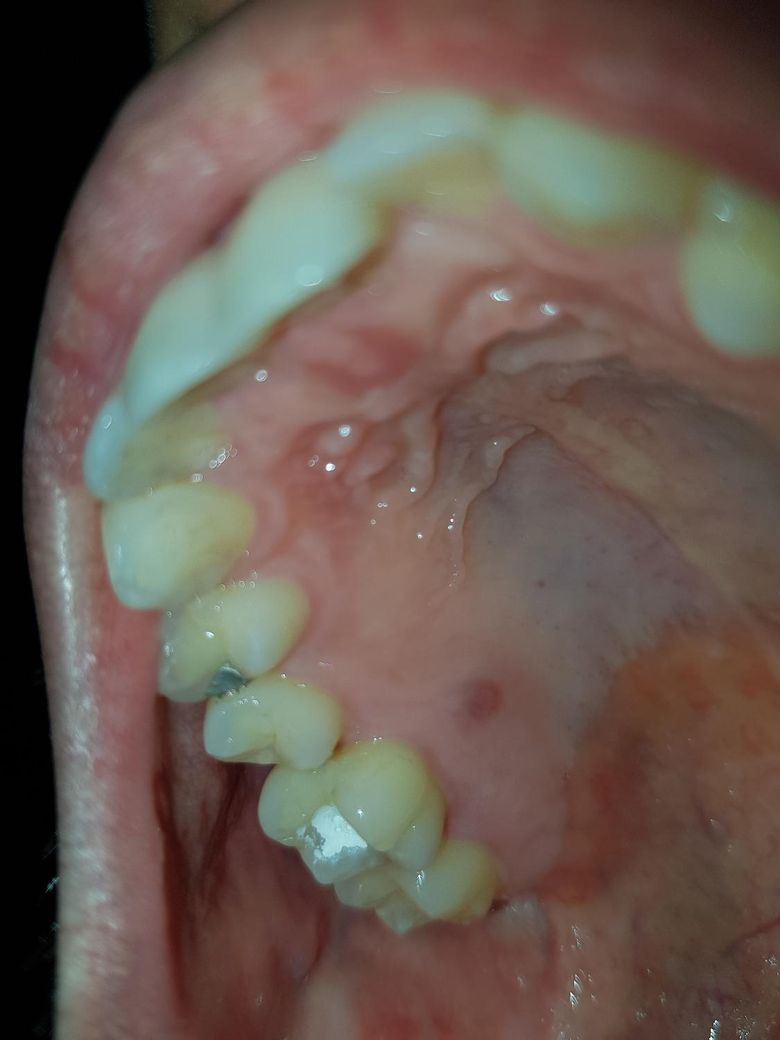

크랙이 있는지 봐주실수있나요 그리고 예후가 불안합니다

신경치료한 이빨쪽에 전에 씹었다 뗄때 통증이 있고나서 2달뒤 급작스럽게 부어서 잇몸수술하고 레진으로때운뒤 1주일만에 입천장으로 농양이생겨 3달뒤 신경치료하게된 상태인데 지금은 시작한지 11일정도 된 상태입니다 6번 갔습니다

제 선생님은 크랙없다 괜찮다하셨는데 전에도 잇몸수술하고 괜찮다해서 레진으로 떼운다음에 1주일만에 농양이 생긴거라 이번에도 소독약때문에 염증이 가라앉은거같지만 빼고 씌우는순간 재발할까봐 걱정이됩니다

문제는...이전에 아말감을 당일치기후 교합이 살짝 안맞았는데 3년쓰면서 마지막에 금간상태로 3달가량썼고

크랙증상으로 간건데 충치가 깊지않은데 잇몸문제다 라고 하심.. 육안검사밖에 방법이 딱히 없고요

사진으로 봤을 때는 구계면으로 금이가 있는 것으로 보입니다. 신경치료를 하고 난 다음에 통증이 심하지 않거나 불편감이 없다면 크라운으로 치아를 씌워서 사용할 수 있습니다. 치아에 생긴 금이 뿌리로 진행되어 생긴 통증이 있다면 치아를 발치해야 하는 경우도 생길 수 있습니다.

크랙치아의 경우는 증상으로 판단을 합니다. 엑스레이 상이나 육안상으로 크랙이 간걸 판별할수 잇을정도면 발치를 해야될 가능성이 더 높습니다 육안상으로는 괜찮아 보입니다.

치아 크랙의 경우 맨눈으로 봤을때 관찰이 어려운 경우가 많습니다 보통 치과에서는 밝은 빛 아래에서 보거나, 메틸렌블루 염색을 해서 관찰합니다